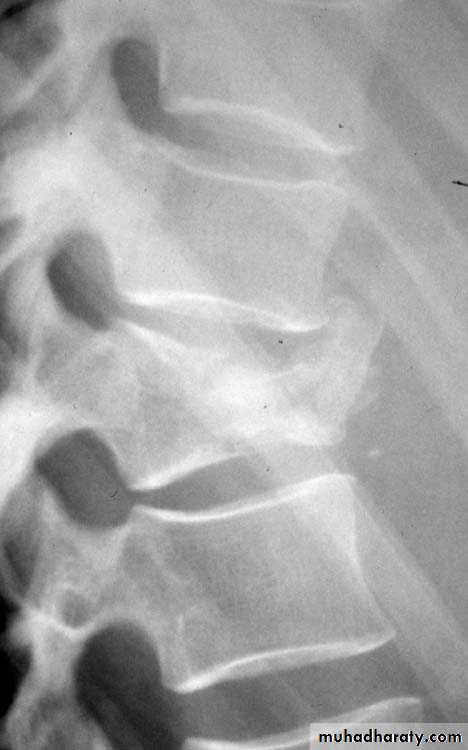

Codfish sign : biconcave appearance of vertebrae seen in osteoporosis and hemolytic anemia: thalasemia and sickle cell